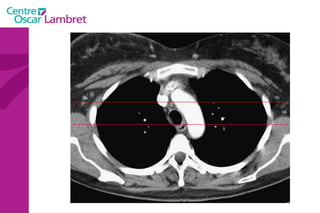

Le médiastin C'est l’espace au centre du thorax. Il est situé en avant de la colonne vertébrale et peut être divisé en plusieurs quadrants.  Il est divisé, par convention, en : médiastin postérieur :  contenant notamment  l’oesophage et l’aorte descendante.  médiastin moyen :  contenant les voies aériennes supérieures : trachée et sa division (carène).  médiastin antérieur :  contenant le cœur, l’aorte ascendante, les artères pulmonaires et la veine cave supérieure.

Le médiastin Le médiastin   antérieur  comprend : L’aorte ascendante Le tronc pulmonaire La veine cave supérieure Les cavités cardiaques sauf l’atrium gauche La loge thymique

Le médiastin Le  médiastin moyen  comprend : La trachée La carène Les pédicules pulmonaires : Les bronches souches Les veines et les artères pulmonaires Le segment horizontal de la crosse de l’aorte Le Tronc Artériel Brachio-Céphalique L’artère carotide primitive gauche La crosse de la grande veine azygos

Le médiastin Le médiastin  postérieur  comprend : Le canal thoracique La grande veine azygos et les veines hémi azygos L’œsophage L’aorte descendante et ses branches

Le médiastin

La ligne médiastinale antérieure (jonction des deux languettes pulmonaires antérieures avec 4 feuillets pleuraux en arrière du sternum et en avant du médiastin).  •  La ligne médiastinale postérieure (jonction des deux languettes pulmonaires postérieures et supérieures en arrière du médiastin). Le médiastin

Ligne médiastinale postérieure Ligne médiastinale antérieure Le médiastin